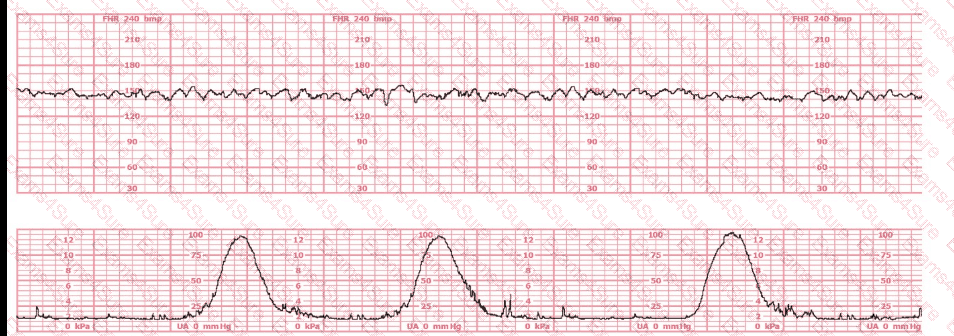

A fetal heart rate pattern shows no accelerations or decelerations. It would be interpreted as a Category II pattern if it occurred with: